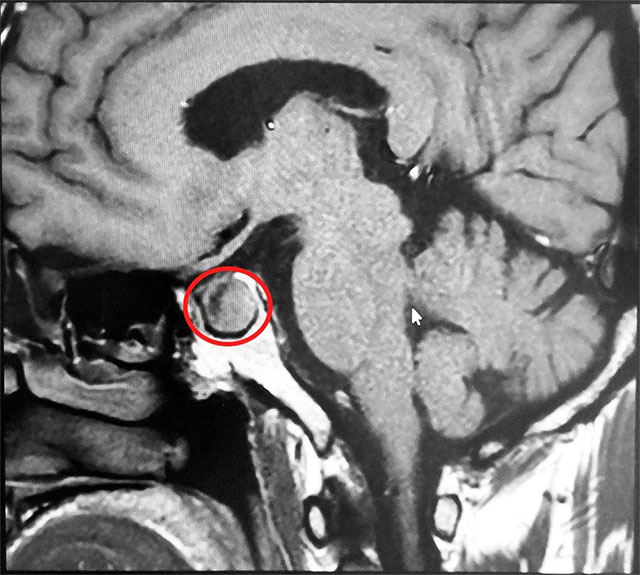

▲ 垂體大腺瘤超蝶鞍生長

患者MR鞍區(qū)MRI平掃+增強提示垂體占位,大小約1.7cm*1.4cm,專家考慮垂體腺瘤伴囊變。6B病區(qū)潘仁龍主任指出,該腫瘤屬于罕見的垂體促甲狀腺激素大腺瘤,對周圍正常組織壓迫導致患者頭疼,已影響患者正常生活及自理能力,使患者精神壓力日益增加,手術指征明確,應盡快行手術治療。